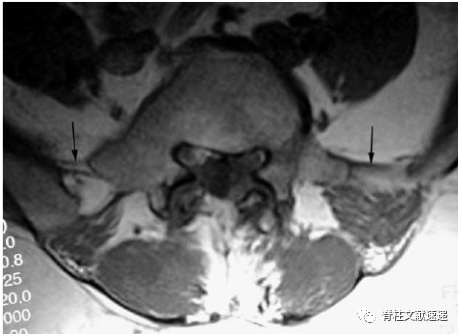

Hughes RJ等人的研究中提出,通过在MRI上识别髂腰韧带来确定椎体节段,因髂腰韧带起自L5横突。MRI上可以清除的看到髂腰韧带为L5横突延伸至髂后内侧嵴的单或双低信号带,如图6所示,当髂腰韧带出现在移行椎头侧椎体时,移行椎被认定为S1。如图7所示,当髂腰韧带出现在移行椎水平时,移行椎被认为L5。如图8所示,当没有找到在正常的髂腰韧带时,移行椎也被认定为L5,在这种情况下,我们假定横突的增宽增大导致较小的韧带发育。

图7注:T1加权像轴向MRI结果显示当移行椎水平识别到髂腰韧带(箭头处)时,移行椎被认为是L5。